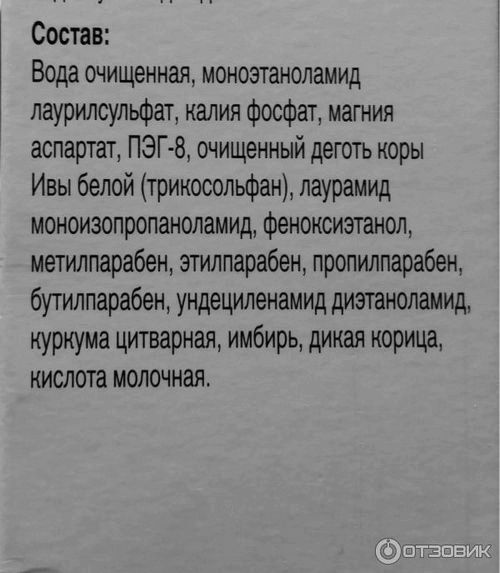

Склад був зазначений на коробці:

розбирати я його не стану, але в очі відразу кидаються парабени і sls.